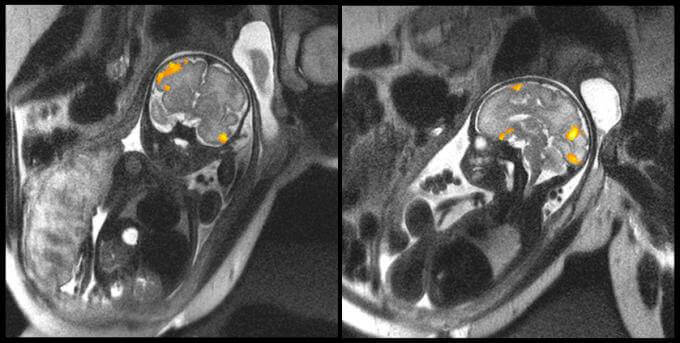

Na imagem acima, podemos ver a ressonância magnética de um feto de 20 semanas e o outro de 40. São imagens fornecidas pela Faculdade de Medicina da Universidade Estatal de Wayne (Michigan, Estados Unidos) que ilustram com clareza como é a atividade cerebral destes dois bebês no útero de sua mãe.

Um dos principais objetivos dos cientistas com esse tipo de testes foi estudar como os neurônios dos bebês se conectam durante as últimas semanas de gestação. Os dados obtidos revelaram aspectos que até agora eram desconhecidos sobre os bebês prematuros.

No entanto, esta nova evidência deixa claro que a baixa neuroconectividade é demonstrada já no interior do útero materno, e que essa falta de conexão entre os neurônios é muito evidente na área de Broca, ou seja, bem na área relacionada com o processamento da linguagem.